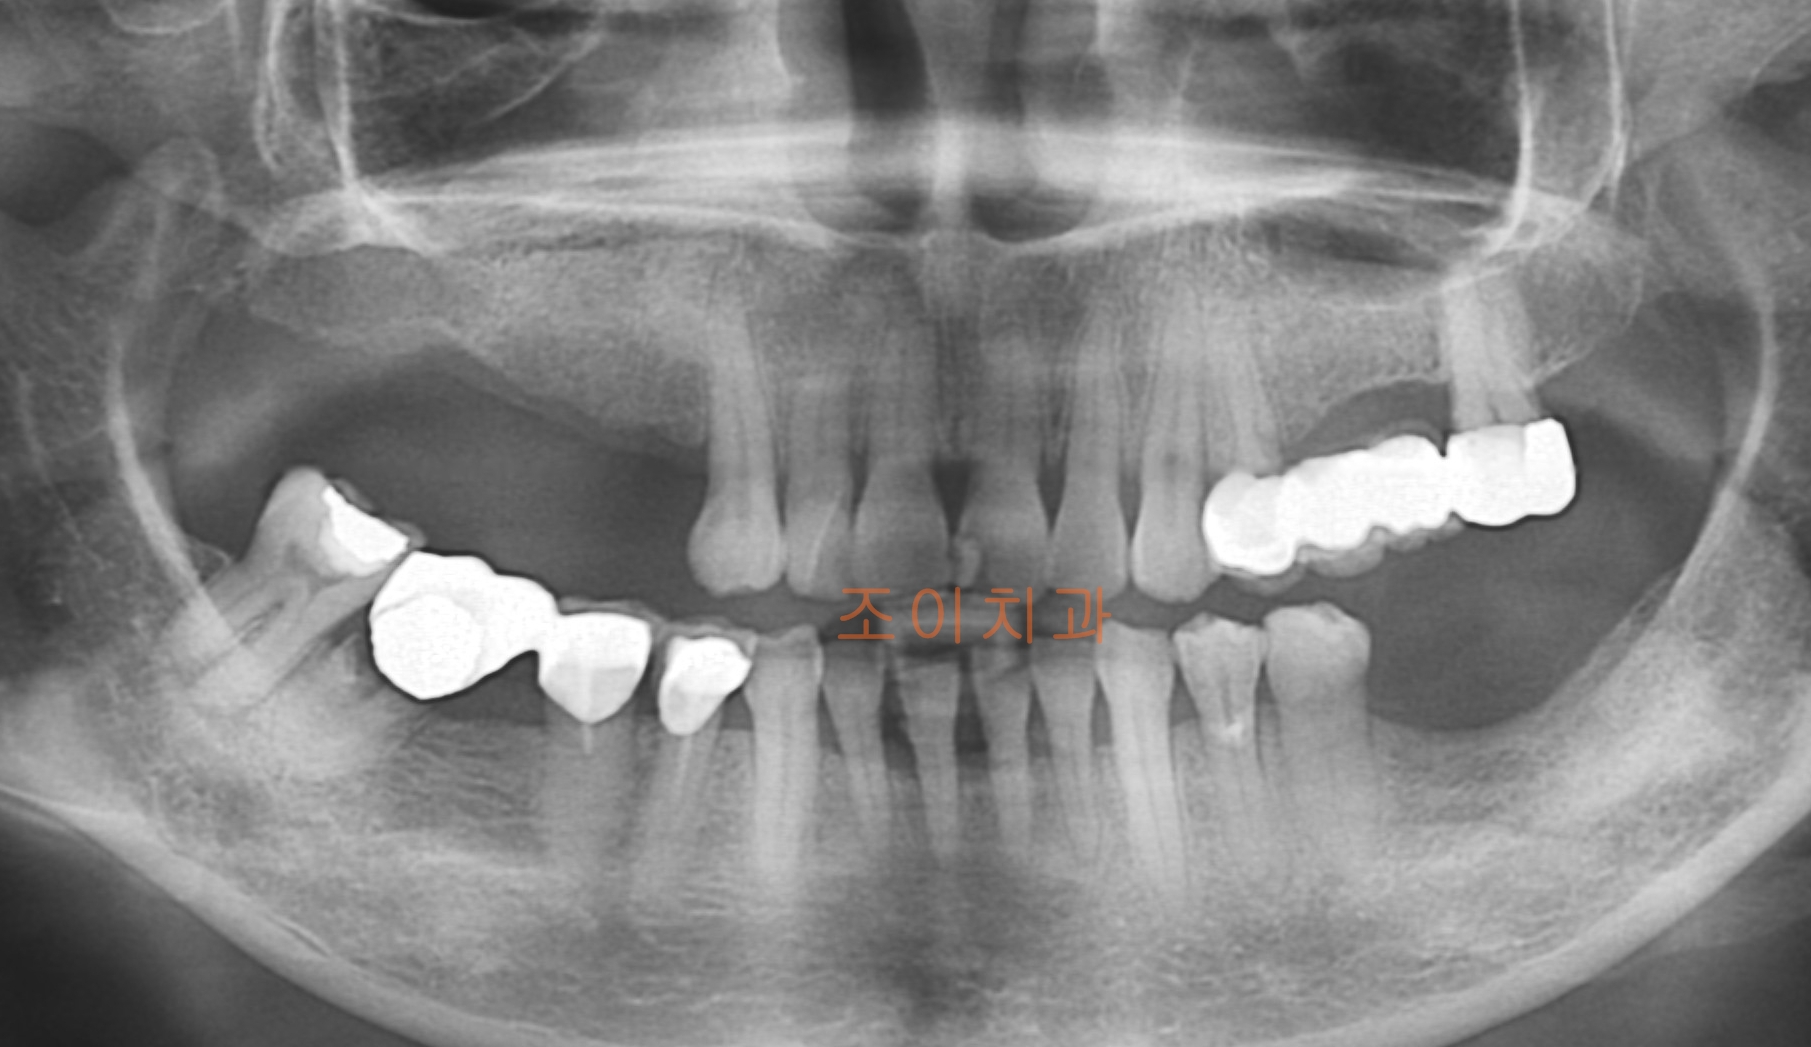

[임플란트] 제목 : 앞니 보철 및 임플란트

임플란트 상하